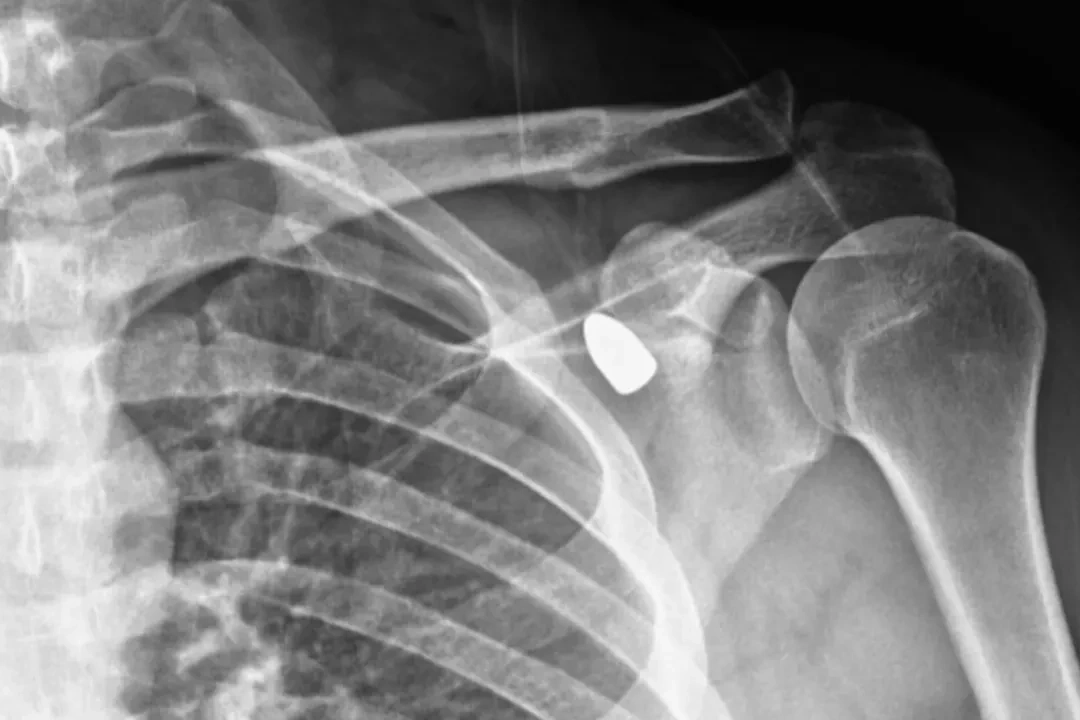

Konya’da okul müdürü Celal Şenyiğit altı yıl önce çay ocağında otururken omzuna yorgun mermi isabet etti. Ancak yapılan muayenelerde merminin yeri nedeniyle hareket kaybı riski taşıdığı tespit edilince herhangi bir operasyon yapılmadı.

6 yıl boyunca omzundaki mermi ile yaşayan Şenyiğit, ağrı ve sertlik şikayetiyle Akşehir Devlet Hastanesine başvurdu. Yapılan muayenelerde koltuk altındaki kitlenin, omzuna saplanan yorgun mermi olduğu tespit edildi. Mermi, gerçekleştirilen operasyonla çıkarıldı. Şenyiğit, olayla ilgili şikayetçi olduğunu, çıkarılan merminin incelemeye gönderildiğini söyledi.